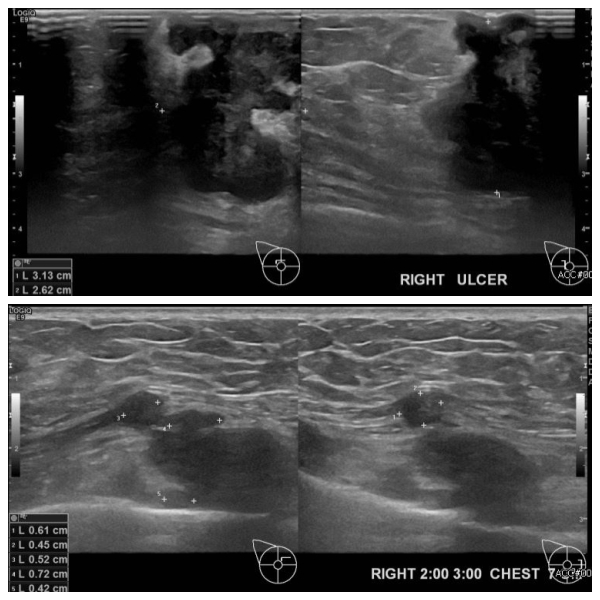

유방멍울 조직검사 권유 받아 내원하신 60대 여성분으로 본원 초음파상 우측 상외측과

우측 2시에서 3시방향에 의심스러운 멍울 조직검사 시행하여 각각 우측 침윤성 유관암

진단되었습니다.